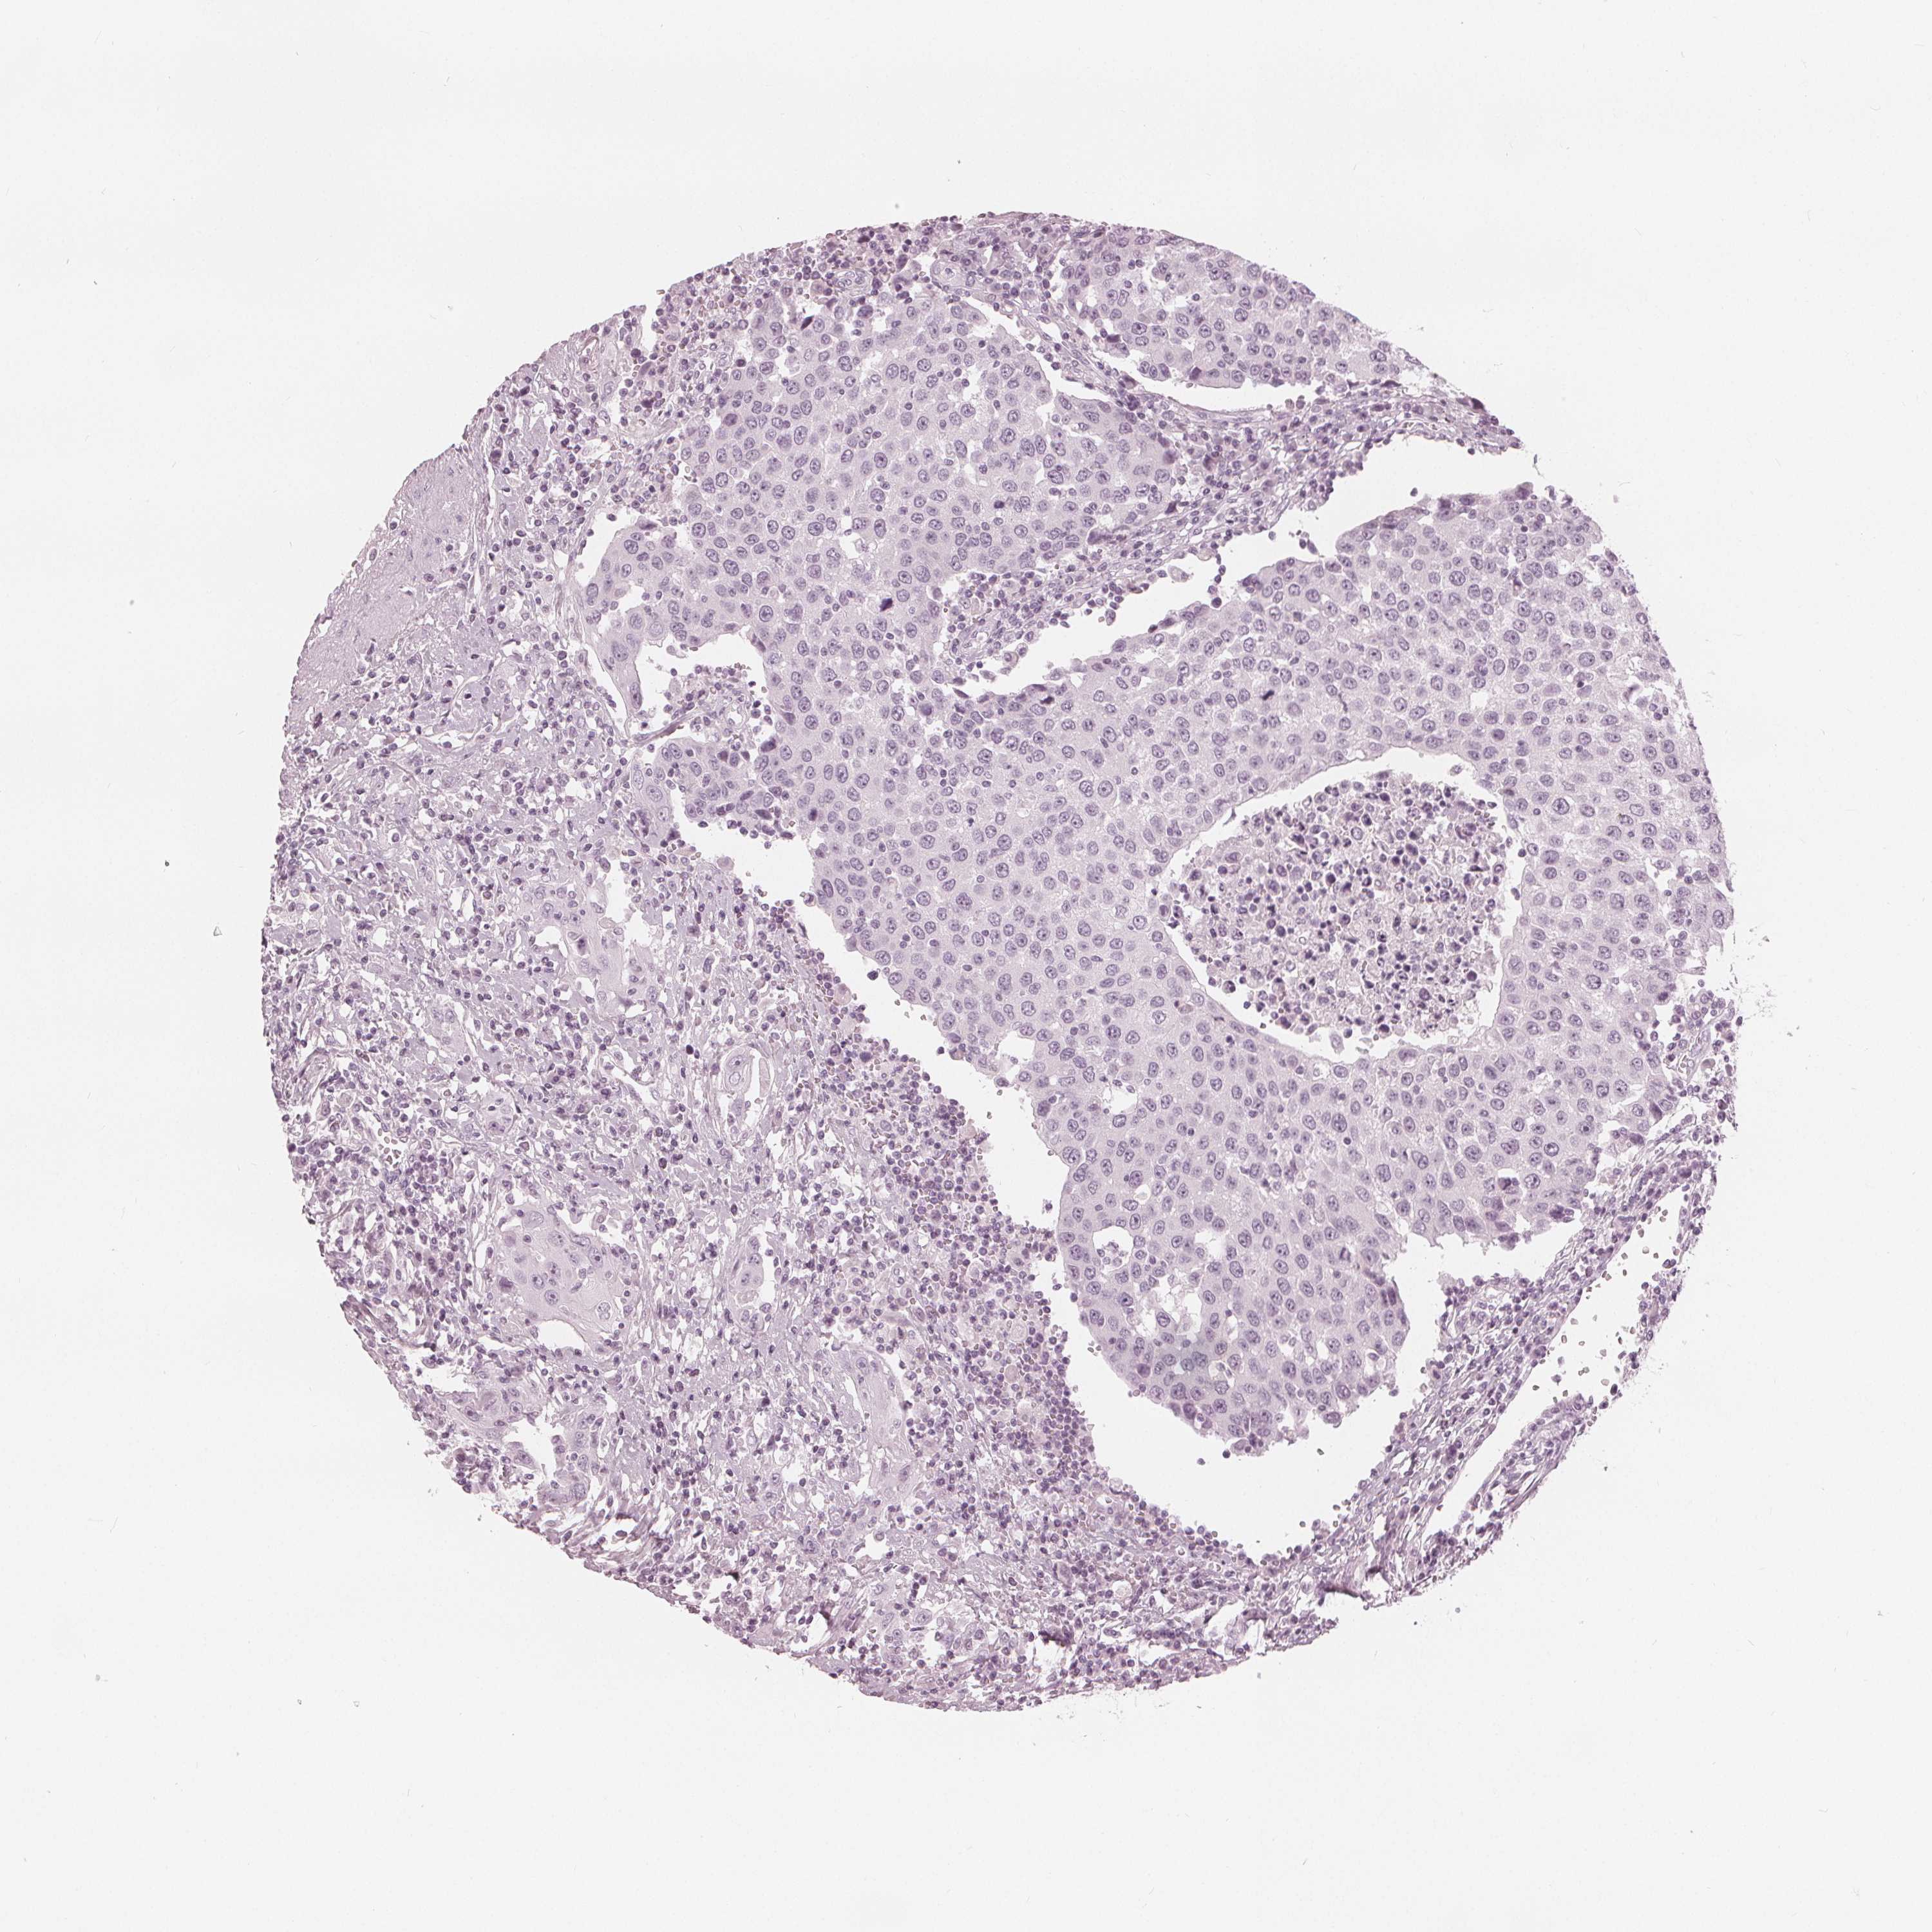

UROTHELIAL CANCER - Protein expressioni

A mouse-over function shows sample information and annotation data. Click on an image to view it in a full screen mode. Samples can be filtered based on level of antibody staining by selecting one or several of the following categories: high, medium, low and not detected. The assay and annotation is described here.

Note that samples used for immunohistochemistry by the Human Protein Atlas do not correspond to samples in the TCGA dataset.

Antibody stainingi

Antibody staining in the annotated cell types in the current human tissue is reported as not detected, low, medium, or high, based on conventional immunohistochemistry profiling in selected tissues. This score is based on the combination of the staining intensity and fraction of stained cells.

Each image is clickable and will lead to virtual microscopy that enables deeper exploration of all samples and also displays staining intensity scores, fraction scores and subcellular localization as well as patient and tissue information for each sample.

Antibody HPA020108

Antibody HPA029473

Antibody CAB016762

Staining

High

Medium

Low

Not detected

Intensity

Strong

Moderate

Weak

Negative

Quantity

>75%

75%-25%

<25%

None

Location

Nuclear

Cytoplasmic/membranous

Cytoplasmic/membranous,nuclear

Urothelial carcinoma, High grade

Urothelial carcinoma, NOS

Urothelial carcinoma, Low grade